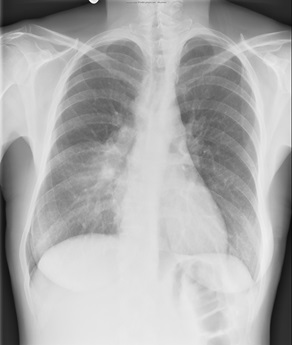

Examen clinique : adénopathie sus-claviculaire gauche, présence de sueurs nocturnes depuis un mois.

Hémogramme : hémoglobine 11.2 g/L, GB 7.9 G/L, lymphocytes 1.4 G/L, albumine 32 g/L, VS 98 mm.

Biopsie d’une adénopathie cervicale: lymphome de Hodgkin classique sclérose nodulaire riche en cellules tumorales.

Fibroscopie bronchique : compression extrinsèque de la lingula, biopsies bronchiques ne montrent pas d’infiltration tumorale.

Stade IV forme thoracique, atteinte médiastinale volumineuse et pulmonaire. Les examens d’imagerie ne montrent pas d’extension sous-diaphragmatique.

| Avant traitement | Après BEACOPP renforcé x 2 cycles Masse médiastinale dont le SUVmax est comparable au bruit de fond hépatique, correspondant à une réponse métabolique complète |

Résultat : la réponse métabolique complète après BEACOPP renforcé 2 cycles conduit à poursuivre le traitement par ABVD x 4 cycles selon l’essai AHL2011, avec évaluation après ABVD 2 cycles et en fin de traitement. La TEP-TDM montre une masse médiastinale résiduelle de taille 36 x 42 mm inchangée entre l’évaluation après 4 cycles et en fin de traitement, avec maintien de la réponse métabolique complète, correspondant à une diminution de 88%. Classement rémission complète incertaine selon les critères de Cheson 1999 et à une rémission complète selon les critères IWG 2007.